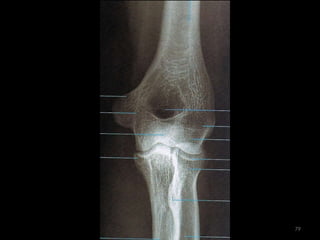

cotovelo61

Incidência AP de cotovelo62

63

64

Incidência lateral cotovelo (látero-medial)65